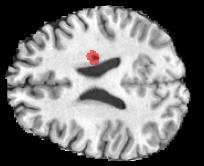

Machine learning models are typically deployed in a test setting that differs from the training setting, potentially leading to decreased model performance because of domain shift. If we could estimate the performance that a pre-trained model would achieve on data from a specific deployment setting, for example a certain clinic, we could judge whether the model could safely be deployed or if its performance degrades unacceptably on the specific data. Existing approaches estimate this based on the confidence of predictions made on unlabeled test data from the deployment's domain. We find existing methods struggle with data that present class imbalance, because the methods used to calibrate confidence do not account for bias induced by class imbalance, consequently failing to estimate class-wise accuracy. Here, we introduce class-wise calibration within the framework of performance estimation for imbalanced datasets. Specifically, we derive class-specific modifications of state-of-the-art confidence-based model evaluation methods including temperature scaling (TS), difference of confidences (DoC), and average thresholded confidence (ATC). We also extend the methods to estimate Dice similarity coefficient (DSC) in image segmentation. We conduct experiments on four tasks and find the proposed modifications consistently improve the estimation accuracy for imbalanced datasets. Our methods improve accuracy estimation by 18\% in classification under natural domain shifts, and double the estimation accuracy on segmentation tasks, when compared with prior methods.